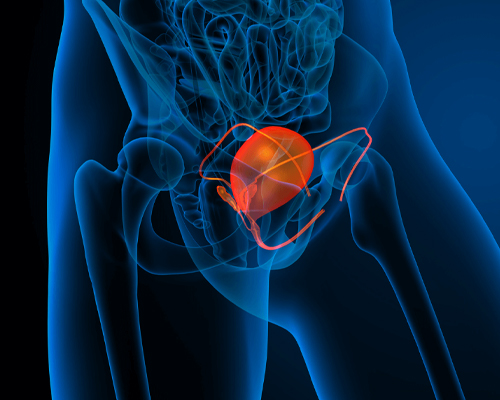

Kidney stone disease is a common urological condition in which hard mineral deposits form in the kidneys or urinary tract. These stones can cause severe pain, urinary obstruction, recurrent infections, and may lead to kidney damage if not treated on time.

He had extensive and grounded training in dealing with management of patients with kidney stone disease, urological malignancies, male sexual dysfunction, urethral stricture disease, prostate related disease and Renal transplant. His training also includes management of simple and complicated UTI, Urosepsis, Neurogenic Bladder, OAB, UAB, Renal Trauma, urinary incontinence, female Urology, Bladder pain syndrome.